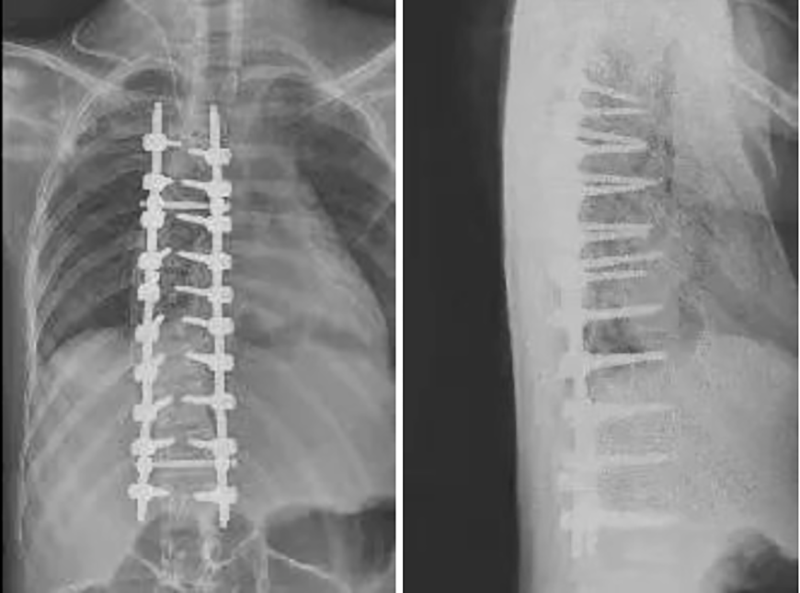

隨后,脊柱外科團隊制定了科學(xué)、周密的手術(shù)方案,針對手術(shù)的風(fēng)險、并發(fā)癥、預(yù)后等情況也進行了全面的評估。在完善相關(guān)術(shù)前準(zhǔn)備后,在麻醉科和神經(jīng)電生理監(jiān)測醫(yī)生等的精心配合下,在各學(xué)科的全力支持與配合下,脊柱外科團隊順利完成了脊柱側(cè)彎矯形手術(shù)。術(shù)后患者生命體征平穩(wěn),平安返回病房。

術(shù)后,在脊柱外科醫(yī)護團隊的精心治療和護理下,蕾蕾恢復(fù)良好,術(shù)后7天即可佩戴胸腰支具首次下地活動,軀干可以挺直,且明顯感到呼吸順暢。更讓蕾蕾和家人驚喜的是,手術(shù)后蕾蕾的身高比原來足足高了6厘米,“重獲新生”后的蕾蕾終于能夠享受正常人的生活,繼續(xù)完成自己的學(xué)業(yè)。